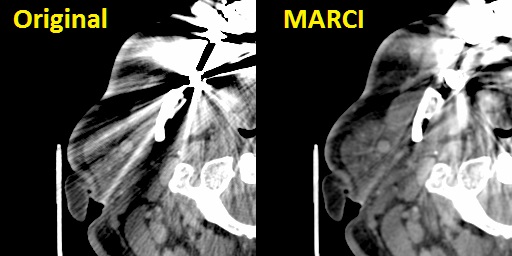

- Metal Artefact Reduction in CT Scans - We have considerable experience of head and neck work and our 3D modelling processes in this region need to recover high fidelity profiles of bony structures of the jaws. Unfortunately many people have extensive metalwork in their teeth (amalgam fillings, crowns, etc.) which cause severe distortions in CT images due to over-scattering and lack of transmittance of the X-ray beams in the scanner. This results in gross distortions of the reconstructed images (an example is shown in the image at the top of this page - middle, top - and also in the figure below, left). Although many algorithms to reduce such artefact have been published since the mid 1980's we found none of them met out specific needs for reduction of severe (as opposed to only moderate) dental artefacts or others were made for use with specific scanners or required access to the raw scanner data. We rarely get access to raw CT scanner data and we use CT images from a variety of sources supplied to us by our clients. For this reason we developed our own in-house algorithm specially designed to deal with severe dental metalwork-induced artifacts. This is a non-iterative algorithm based on non-linear interpolation and inspired by the Kriging technique used in geosurveying. We call this the MARCI™ algorithm (Metal Artefact Reduction by Constrained Imputation). An example result of applying our MARCI algorithm is shown in the image at the top of this page (middle, bottom) and in the figure below (right). No algorithm can completely remove such severe artefact but our method reveals sufficient hidden detail for us to make good quality 3D models even from severely degraded images. Please note: We do not report CT scans or other radiology studies - we only process images as a service. MARCI algorithm processing is made available for research purposes only because it does not have any regulatory approval for clinical use. Below is a close-up of soft tissue windows from an original CT scan with severe metal artefacts (left) and the result of our MARCI algorithm on the same scan (right) showing not only reduced distortion of the bone profiles (which is what the algorithm was primarily designed for) but the added bonus of increased visibility of soft tissue structures as well.